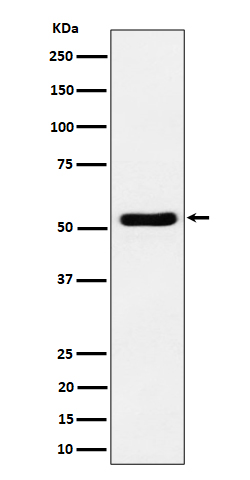

分类: 科研抗体货号: P20021别名: Antigen NY-CO-13; Cellular tumor antigen p53; Phosphoprotein p53; TP53; Tumor suppressor p53应用: WB,IP,IF反应种属: Human,Mouse,Rat